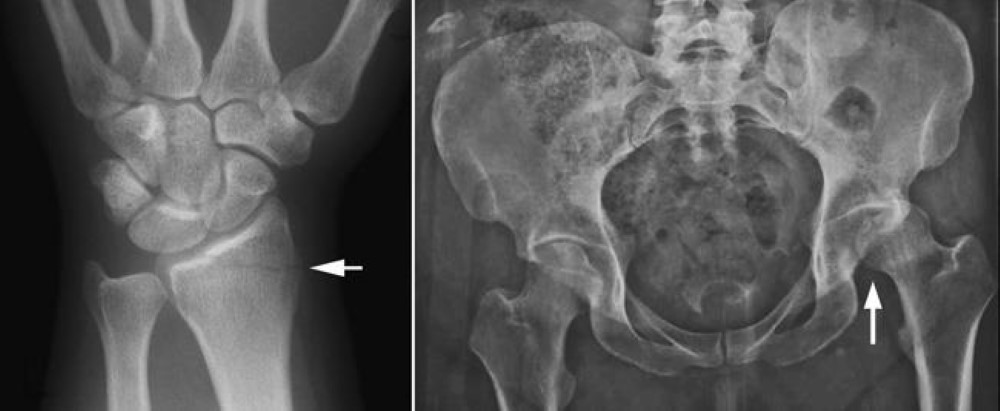

X-rays of a broken wrist and a dislocated hip

X-rays are often used to diagnose bone fractures and dislocated joints. The X-rays shown here reveal (left) a distal radius (wrist) fracture and (right) a dislocated hip.

(Left) Reproduced from Johnson TR, Steinbach LS (eds.): Essentials of Musculoskeletal Imaging. Rosemont, IL, American Academy of Orthopaedic Surgeons, 2004, p. 341.